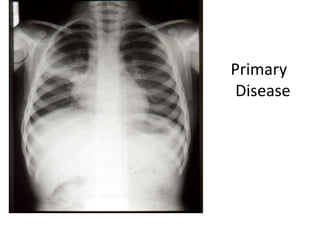

TB – A Multi-system Infection

Primary

Disease